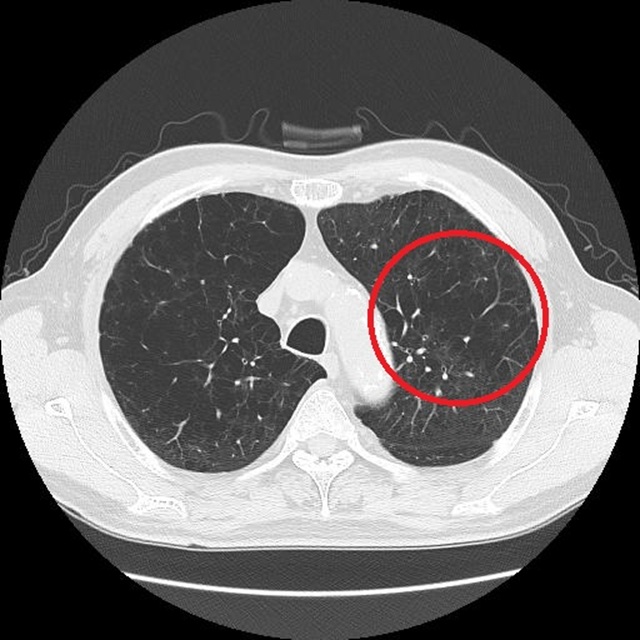

周囲より黒く抜けた部分は肺がない(肺気腫)70代男性重症COPD患者(過去喫煙の経験あり)のCT画像 提供:呼吸ケアクリニック東京